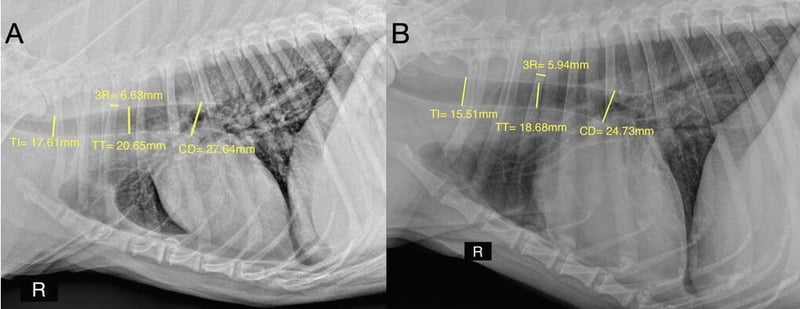

MusculoskeletalMusculoskeletal